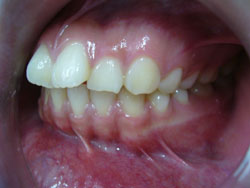

*Hô răng hàm trên, hô hàm trên:

- Hô răng hàm trên và hô hàm trên là một lệch lạc khá phổ biến, làm cho khuôn mặt không thẩm mỹ.

Hô răng hàm trên là tình trạng răng cửa hàm trên trên nghiêng nhiều ra trước, trong khi xương hàm trên vẫn bình thường theo tương quan chiều trước sau.

Hô Hàm trên là tình trạng hàm trên nhô quá về phía trước, hoặc hàm dưới lùi quá về phía sau